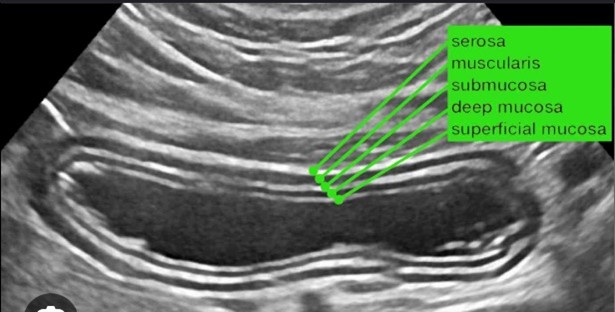

- Interactieve quiz:

De dag werd afgesloten door een quiz waarbij slecht één beeld gepresenteerd werd waarop een ieder middels mobiele telefoon zijn bevinding kon door geven welke op het scherm als een wordle getoond werd. Leuk, maar bovenal leerzaam!